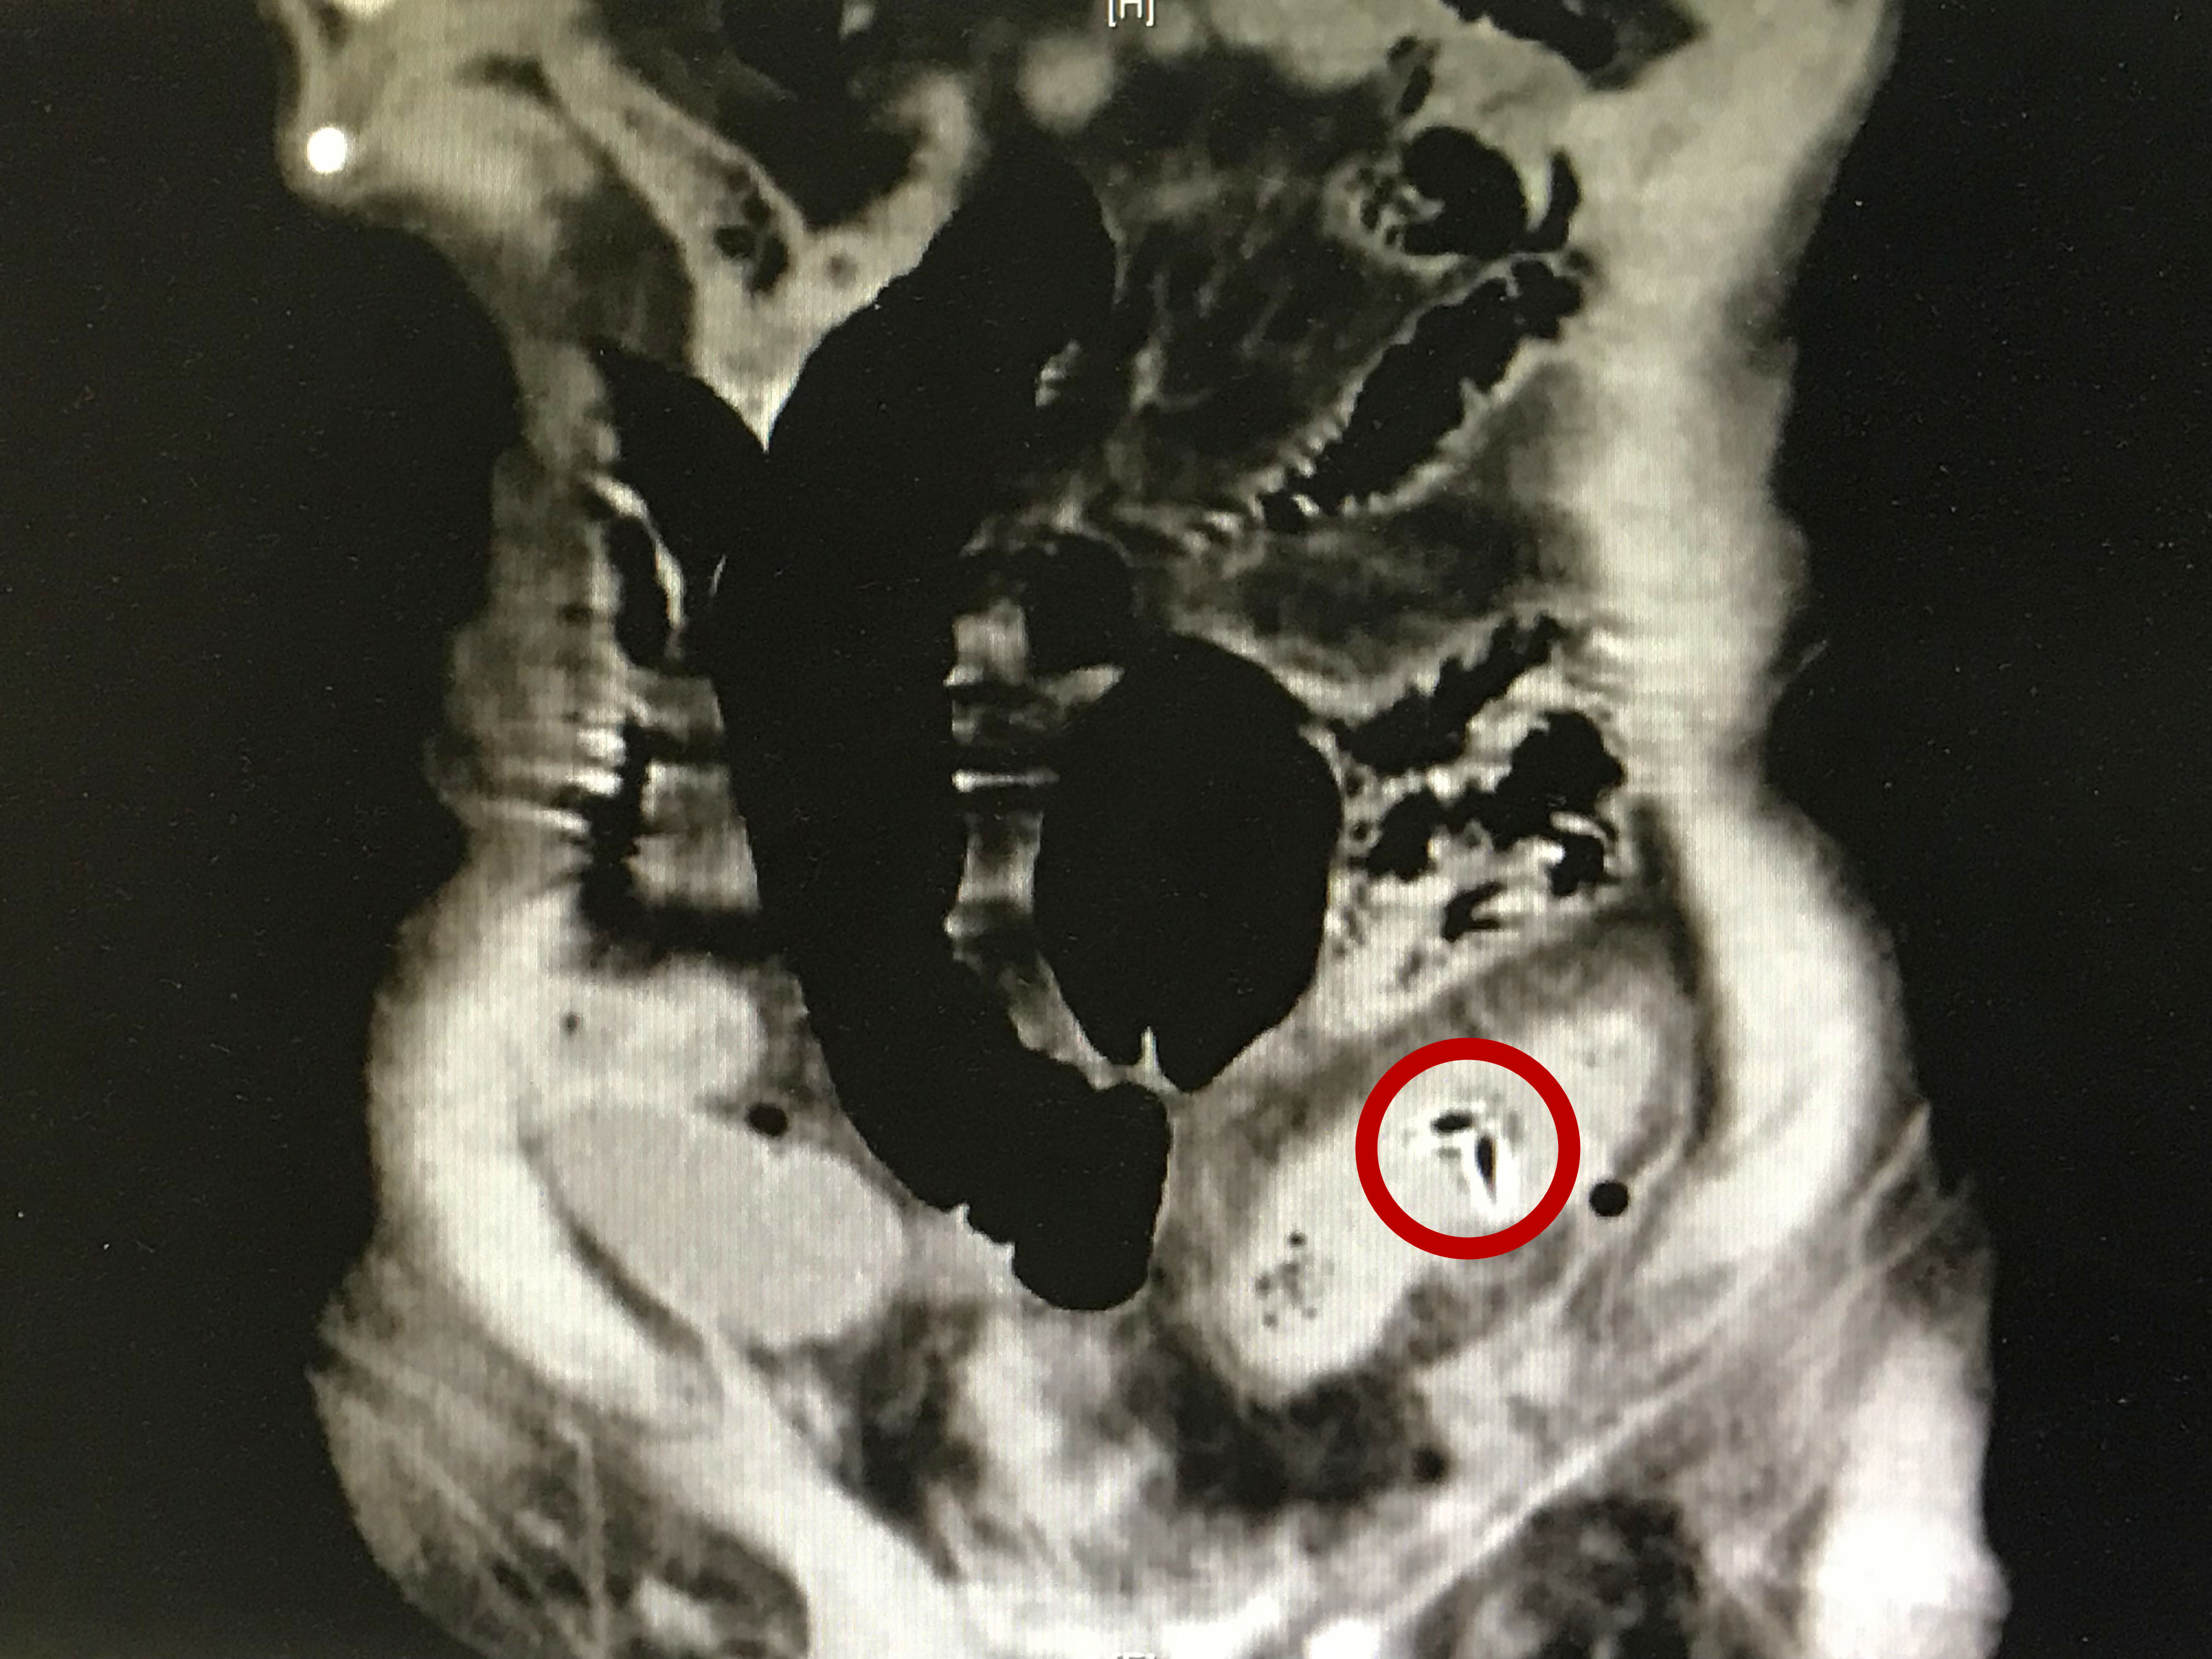

图中红圈所示为枣核

俗话说:“日食三枣,长生不老。”李大爷住在天通苑养老院,平时爱吃枣,今年已经92岁高龄了。来到北京清华长庚医院时,他已腹痛多时。当时值班的急诊外科主治医师张鹏为他做了腹部CT检查,发现老人乙状结肠和降结肠相连的部位被一个尖锐的异物刺穿,造成感染。李大爷的家属担心他年纪大了,承受不了手术,打算先进行保守治疗。但是老人被刺破的伤口附近已经产生炎症和水肿,若进一步发展下去可能会有粪便漏至腹腔导致严重感染甚至危及生命。经过一番协调与讨论,胃肠外科主任李元新果断决定,马上为老人实施手术。

给90多岁的老人实施全麻风险很大,麻醉科会诊后制定了细致的麻醉方案。在麻醉科、手术室的大力配合下,张鹏医师为老人实施了全麻下的肠切除与造瘘术,切掉被刺破的肠管及周围发炎的部分,并取出了罪魁祸首——枣核。与肠吻合术相比,造瘘术极大地降低了老人术后感染、吻合口瘘等风险,并能让他更快恢复饮食,加速康复。经过ICU及胃肠外科的精心护理,目前老人已经顺利恢复出院。